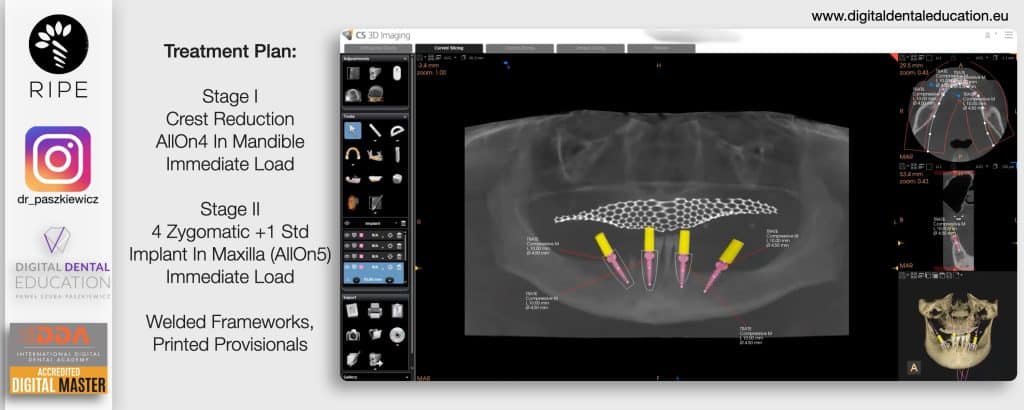

He has invented an AllonX non-impression protocol leading to final restorations post immediate implant full-arch loading, incorporated with desktop scanner (MEDIT) and ModJaw capturing of natural patient’s functional and mastication movements.